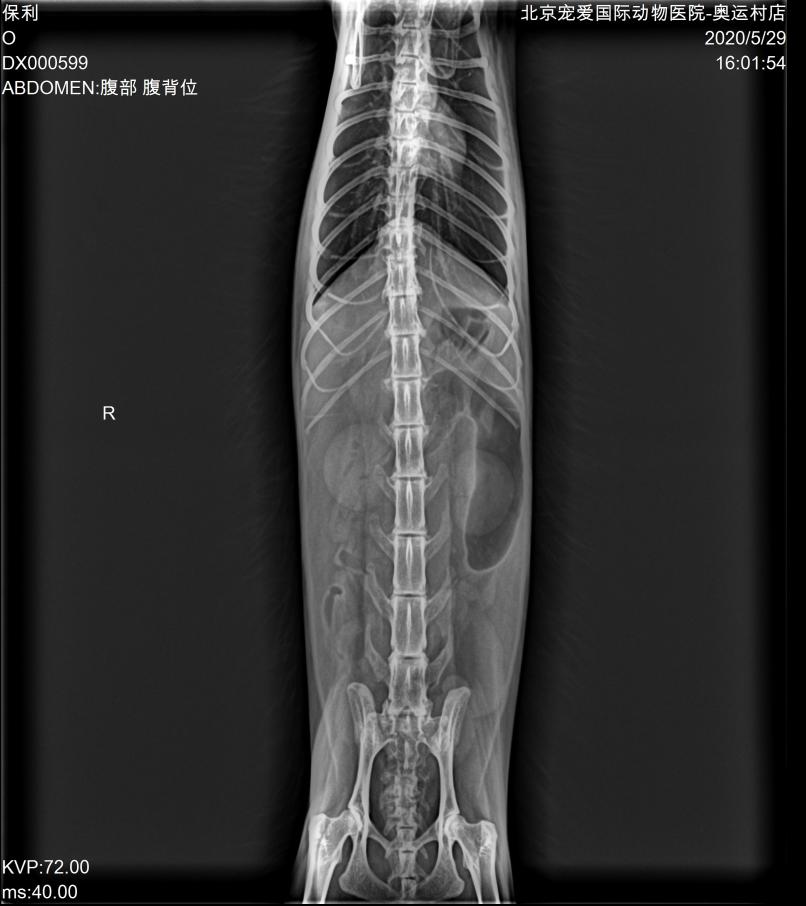

DR:

DR显示胃肠道空虚,未见阳性异物。